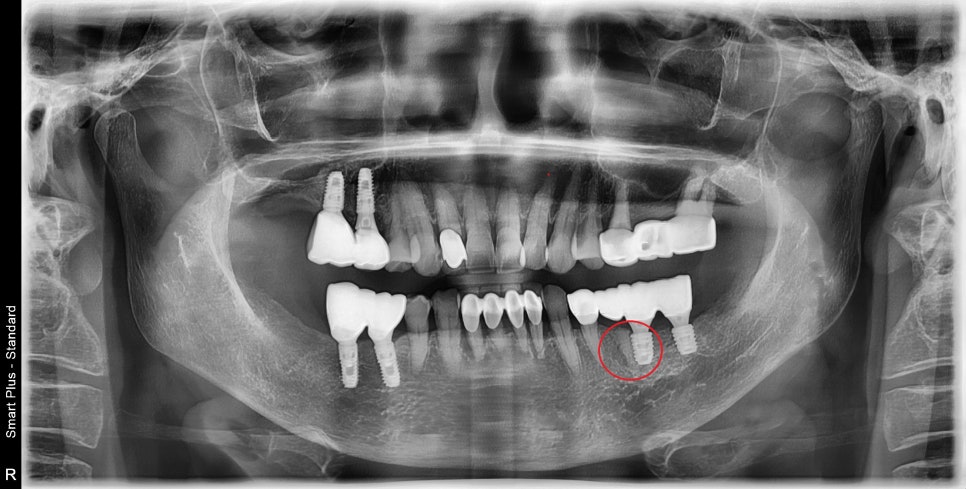

치아 주변 염증으로 인해

치조골이 녹아버린 자리에

치조골 이식술을 동반한

최후방 치아까지 회복을 한 상태입니다.

과거의 저작시 불편감은 다 사라진 상태입니다.

이렇게

어금니 하나 차이지만

저작력 효율적인 면에서는 차이가 납니다.

그렇기 때문에

장기적으로 보았을 때는

수술이 불가능한 경우가 아니라면

최후방 치아까지 회복시켜주는 편이 좋습니다.